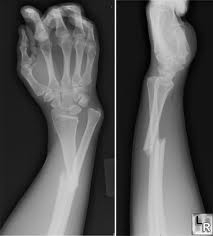

وأشار الدكتور حازم فاروق، استشارى جراحة العظام بطب قصر العينى وسكرتير عام المؤتمر، إلى أن القائمين على المؤتمر سيعقدون ورش عمل ودورات مكثفة لتدريب شباب جراحى العظام على أحدث الوسائل فى علاج الكسور فى التخصصات المختلفة فى جراحة العظام، مثل إصابات الملاعب والطب الرياضى وجراحات اليد والجراحات الميكروسكوبية وجراحات الحوض وأمراض عظام الأطفال، وأحدث ما توصل إلية العلم والتقنيات الحديثة فى مجال إصابات حوادث الطرق.